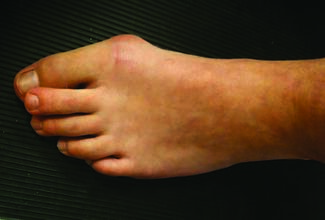

Over the past decade or so, I have written several articles regarding bunions, their treatment options, including the best surgical option for each type of hallux valgus, and why. The overall solution in my hands for hallux valgus deformity...